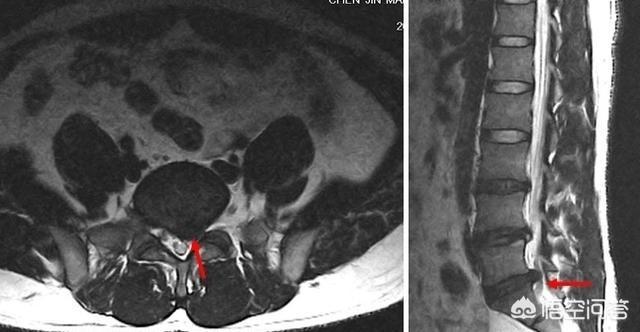

臀部后侧和腿后侧疼痛可以是S1神经的放射区域,当它出现疼痛的时候,要先排除是否有L5-S1椎间盘突出,尤其咳嗽打喷嚏会出现腿上疼痛的时候,这时最好直接去医院做一个腰椎间盘CT,进一步诊断。

尤其在下腰部用手捶一下,或者俯卧时按压下腰部患侧,可以找到一个痛点,按压会引起臀部后侧和腿部后侧的放射痛和平时症状一致,影像学也发现有L5-S1椎间盘突出同侧神经根受压,基本可以确诊。